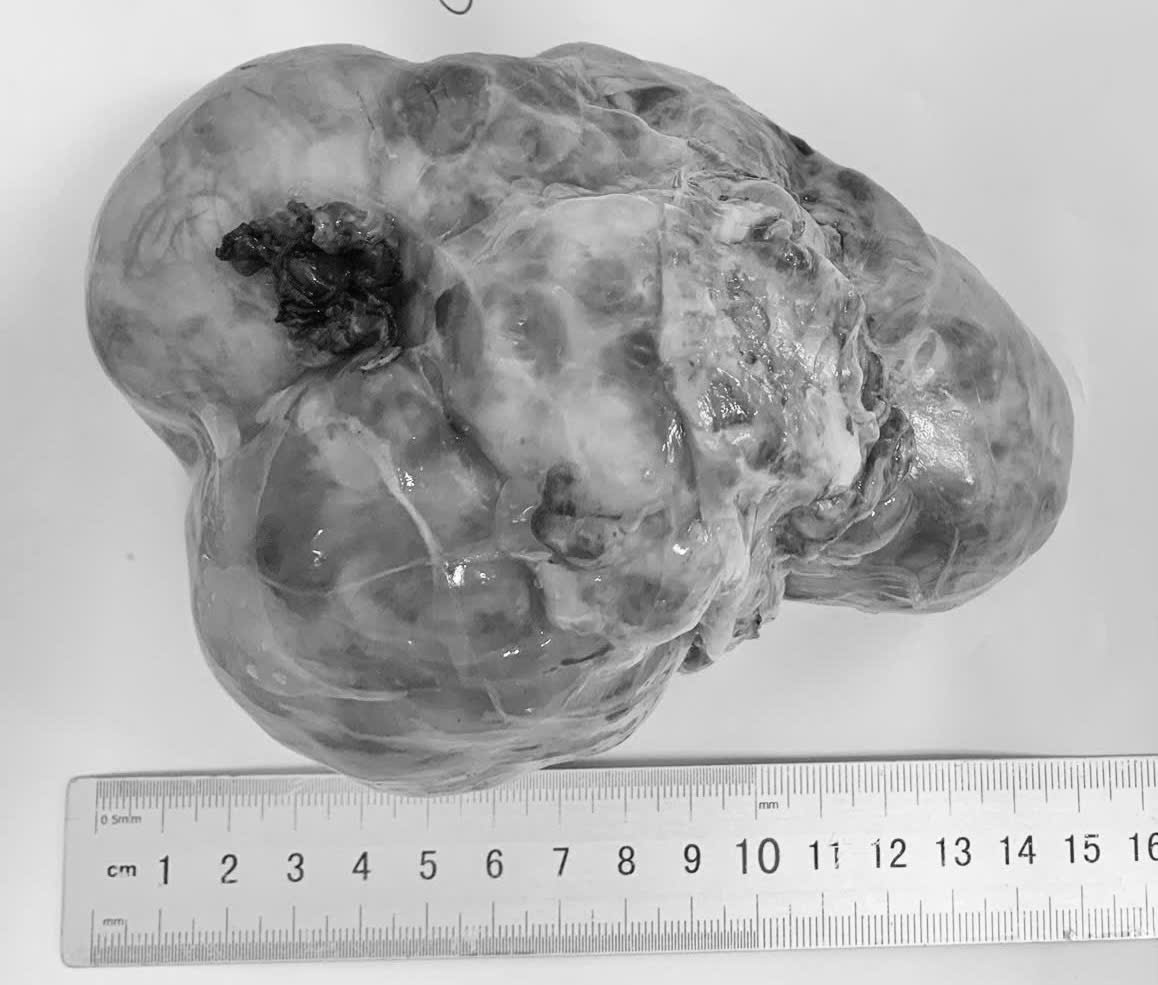

Các bệnh nhi được phát hiện khi khối u đã lớn – Ảnh: T.H.

Theo khoa ngoại Bệnh viện Phụ sản – Nhi Đà Nẵng, ba bệnh nhi vừa được phẫu thuật gồm trẻ 14 tháng tuổi mắc u nguyên bào thận (Wilms), trẻ 4 tuổi mắc u nguyên bào thần kinh, trẻ 5 tháng tuổi mắc u quái ổ bụng cùng quê Quảng Ngãi. Đây đều là những khối u có thể gặp ở trẻ em, trong đó có loại ác tính và nguy cơ tiến triển nhanh.

Đáng chú ý, các trường hợp này đều được phát hiện khi khối u đã lớn, gây khó khăn cho điều trị và làm tăng nguy cơ biến chứng.